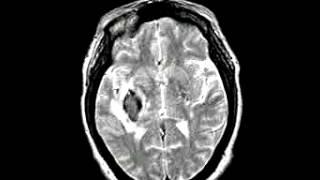

Cerebrovascular Disease Multiple embolic infarction, diffusion and FLAIR imaging

Dr Dong Kyun Kim. Смотреть видео: Degenerative Disease Alzheimers Dementia, Metastatic Carcinoma Of The Colon Spatial, Cerebrovascular Disease Fatal Stroke, Neoplastic Disease Metastatic Adenocarcinoma.